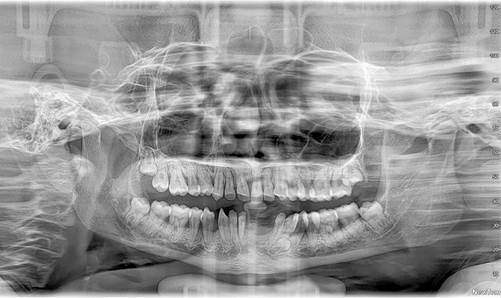

En la radiografía panorámica se evidencia los cuatro terceros molares, un supernumerario compatible por su forma y posición con canino inferior. La altura de hueso maxilar y mandibular es reducida y las piezas dentales son pequeñas. Por lo cual, existe movilidad grado dos especialmente de piezas anteriores tanto superiores como inferiores (Figura 11).

Figura 11. Radiografía panorámica

Al inicio del tratamiento, hace 3 años; se realiza remoción de cálculo y profilaxis semanales con cavitron, cepillos, pasta fluorada y clorhexidina para reducir la inflamación gingival. Luego de este tiempo se ha logrado eliminar todo el cálculo y la movilidad dentaria se mantiene. No hay presencia de caries, pero la inflamación generalizada de la encía no ha disminuido y sigue sangrando a la palpación y manipulación. Con el tratamiento preventivo se evita que haya caries y que pierda piezas dentales por problemas periodontales en lo posterior, el momento que pierda alguna pieza dental, la recesión ósea hará que vaya perdiendo más piezas y no haya la posibilidad de colocar algún tipo de prótesis.